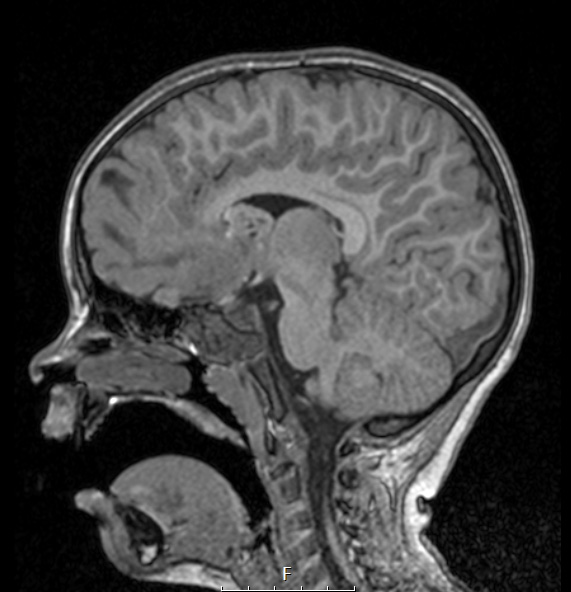

The cortical tuber and SEGA are hypo- and iso-intense, respectfully in this T1-weighted scan.